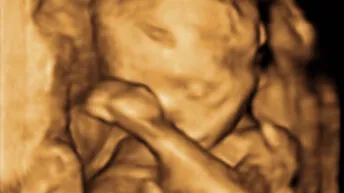

La vita sempre ci sorprende

45^ Giornata per la vita: “La morte non è mai una soluzione”

Vite nascoste